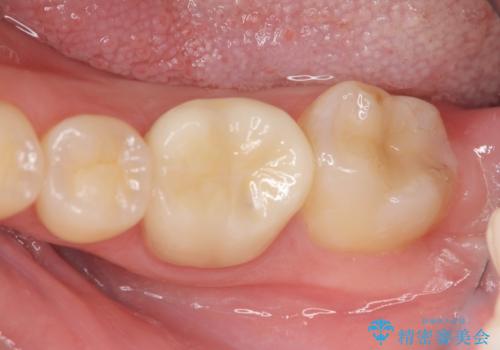

歯冠長の延長を行ったことで、安定したクラウン治療を行うことができました。

- 20.9万円(ジルコニアクラウン・仮歯・セラミックインレー)費用は治療当時の料金となります